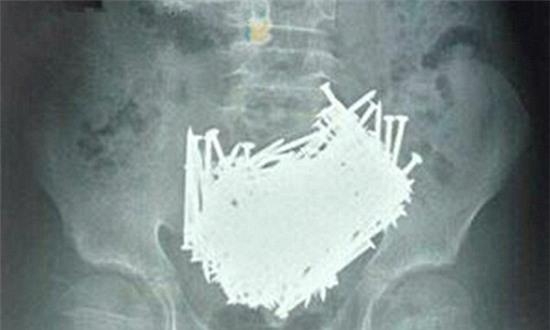

Hình ảnh 200 cây đinh cùng các vật sắc nhọn khác nằm trong ổ bụng của cậu bé.

Sau khi kiểm tra, các bác sỹ đã hết sức sửng sốt khi phát hiện dạ dày cậu bé chứa đầy đinh. Cậu bé ngay lập tức được đưa vào phòng phẫu thuật và lấy ra 200 cây đinh cùng những cây tăm, đá, đồng xu, tổng cộng những thứ đó nặng khoảng 680 gram.